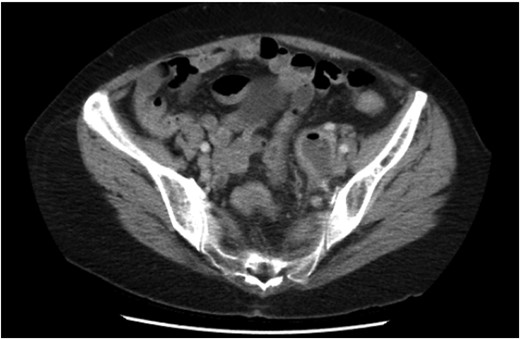

Non-operative management with broad-spectrum IV antibiotics, bowel rest and fluids was trialled. Despite initial clinical improvement with a reduction in pain and down-trending inflammatory markers the patient was once again febrile on day 3 of her admission with plateauing of the inflammatory markers and ongoing pain. A progress CT scan (Fig. 2) showed an unchanged adnexal collection now with sigmoid thickening. Given the findings and lack of clinical improvement, the patient proceeded to have a laparoscopic anterior resection and en bloc left salpingo-opherectomy. Intra-operatively (Figs 3 and 4), the fistula between the sigmoid colon and the left salpinx was very clearly demarcated. Histology confirmed acute diverticulitis locally perforating into the left salpinx and ovary and forming an abscess. An uneventful recovery followed.

Repeat CT scan demonstrating thickening of the sigmoid colon adjacent to the adnexal mass.